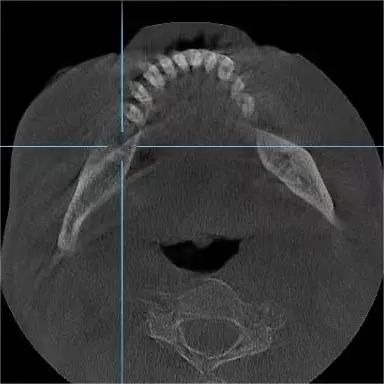

种植专家、口腔科杨彦春主任检查发现其口腔卫生环境较差,缺失的又是需要咀嚼的后牙,建议行种植修复手术。

术中,王先生血压、血氧稳定,仅用半小时,杨彦春主任顺利为其开展两颗种植牙手术。